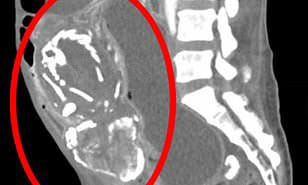

For this woman, the ‘stone baby’ kept compressing the intestine. This caused blockages, meaning her body was no longer able to absorb vital nutrients, leading to...